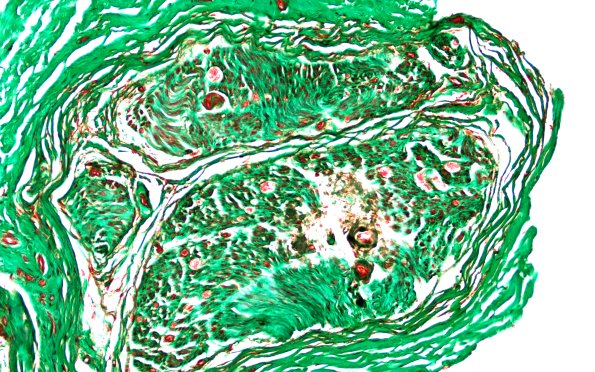

Washington University Experience | PERIPHERAL NEUROPATHY | 14 AMYLOID NEUROPATHY | 13B1 Amyloid Neuropathy TRI (Case 13) 20X 1

13B1,2 Trichrome stain demonstrates that the amyloid is darkly stained gray/black, differing from the green color of the collagen. (Masson trichrome)